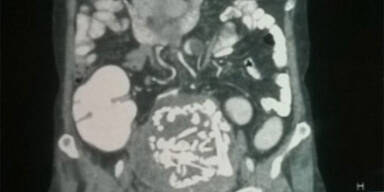

Indische Ärzte haben einer 60-jährigen Frau das Skelett eines Fötus entfernt, den sie 36 Jahre lang in ihrem Körper getragen hatte. Die Frau sei wegen starker Unterleibsschmerzen ins Krankenhaus gekommen, bei der Untersuchung hätten Ärzte dann das versteinerte Skelett entdeckt, sagte Chirurg Murtaza Akhtar von der Uniklinik im zentralindischen Nagpur. Er sprach von einem weltweiten Rekord.

Erst nach Jahrzehnten seien die Schmerzen im Unterleib zurückgekehrt, daraufhin habe sie sich an die Klinik in Nagpur gewandt. Die Ärzte fürchteten zunächst eine Krebserkrankung, doch bei weiteren Untersuchungen entpuppte sich der vermeintlich Tumor als das versteinerte Skelett eines ausgereiften Fötus. "Für uns war das ein medizinisches Wunder, davon hatten wir noch nie gehört", sagte Akhtar. Die Fachliteratur nenne als bisher längsten Fall einer Schwangerschaft außerhalb der Gebärmutter den Fall einer Belgierin, die 18 Jahre lang die Überreste eine Fötus im Körper getragen habe.